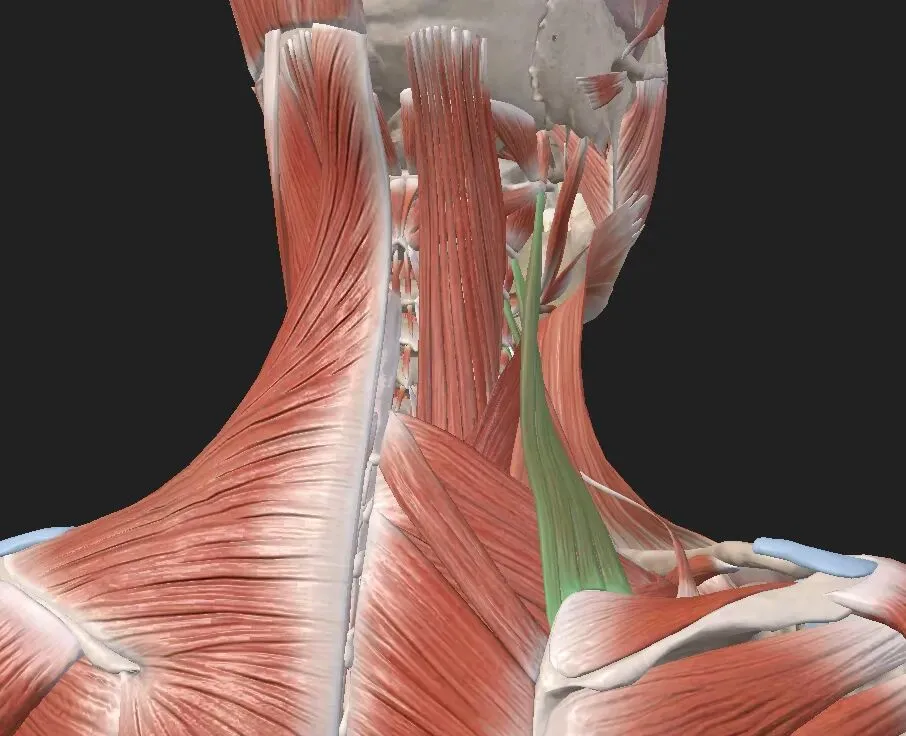

肩胛舌骨肌

起于肩胛骨上缘、肩胛横韧带,止于舌骨体外侧半,分为上腹、下腹,上、下两肌腹间以位于胸锁乳突肌下部深面的中间腱相连;

颈固有筋膜深层在中间腱部有不同程度增厚,形成中间腱鞘,包绕中间腱,当肩胛舌骨肌收缩时起着固定作用,改变其牵引力方向,限制前移。

肩胛舌骨肌由颈襻 C1-3 神经支配,其中颈襻 C1 支配上腹,颈襻 C2-3 支配下腹,且上腹血供主要来自甲状腺上动脉,下腹血供主要来自肩胛上动脉,血供多与支配肩胛舌骨肌的神经一起入肌。